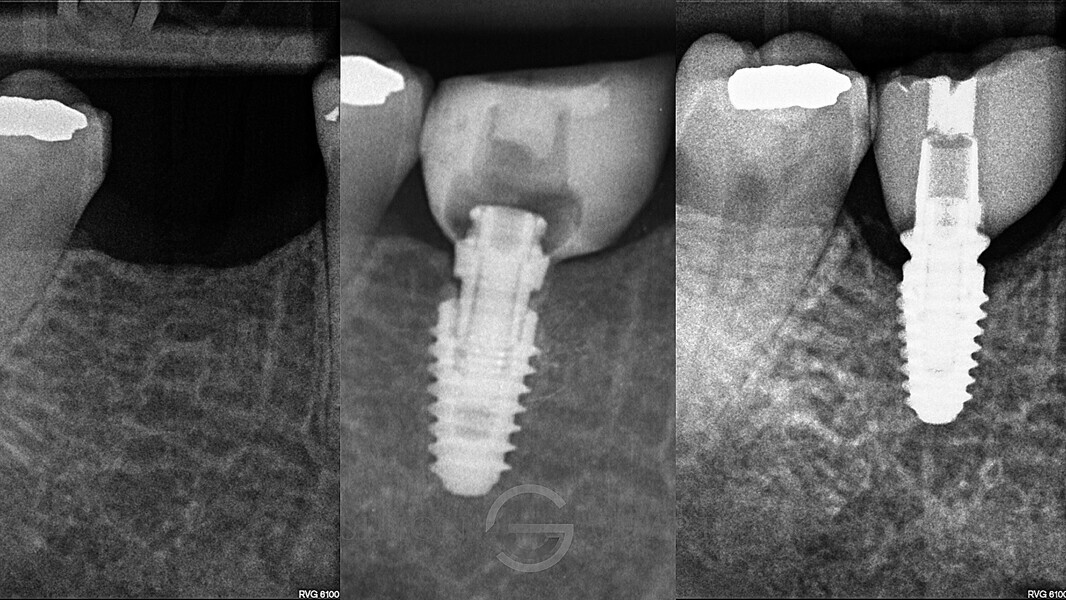

Implant restoration with CEREC